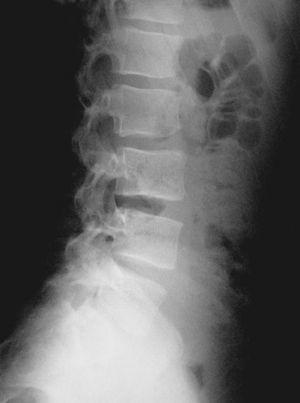

El nuevo estudio radiográfico demuestra espondilólisis L5 derecha y persistencia de integridad del hemiarco izquierdo (figs. 6 y 7). Igualmente, el estudio radiográfico dinámico demuestra establidad completa de la charnela lumbosacra (fig. 8). Por todo ello se planea el alta deportiva, aunque se le recomienda continuar un mes más el tratamiento, demorando el regreso a la práctica deportiva.

Figura 6

Figura 7

Figura 8